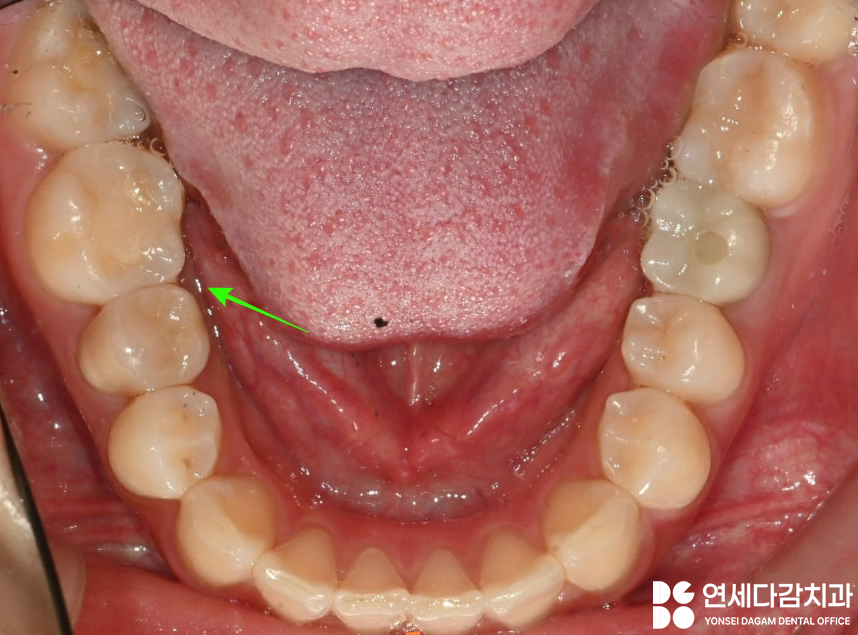

아래 사진은 술 후 8개월이 지난 시점 에서

촬영한 연세다감치과 구강 사진으로,

2024.08.19

역시나 잇몸이 잘 아문 것을 확인할 수 있습니다.

*추후 위치 상 관리가 어렵던

오른쪽 위 아래 사랑니(#18,48번)도

함께 뽑았습니다.